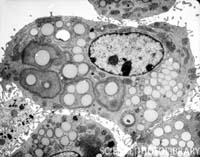

Research projects in this unit have been performed with cooperation of different research Departments or independently, for example: Ultra structure study of spermatogenesis Cells after exposure of morphine in adult male mouse. The tools and technical services for performing the thesis of postgraduate students Of MUMS and other universities have also been carried.

Electron microscope has been used in all areas of biological and biomedical investigations because of its ability to view the finest cell structures, and it is also used as a diagnostic tool in pathology labs for improving diagnostic and treatment of disease.